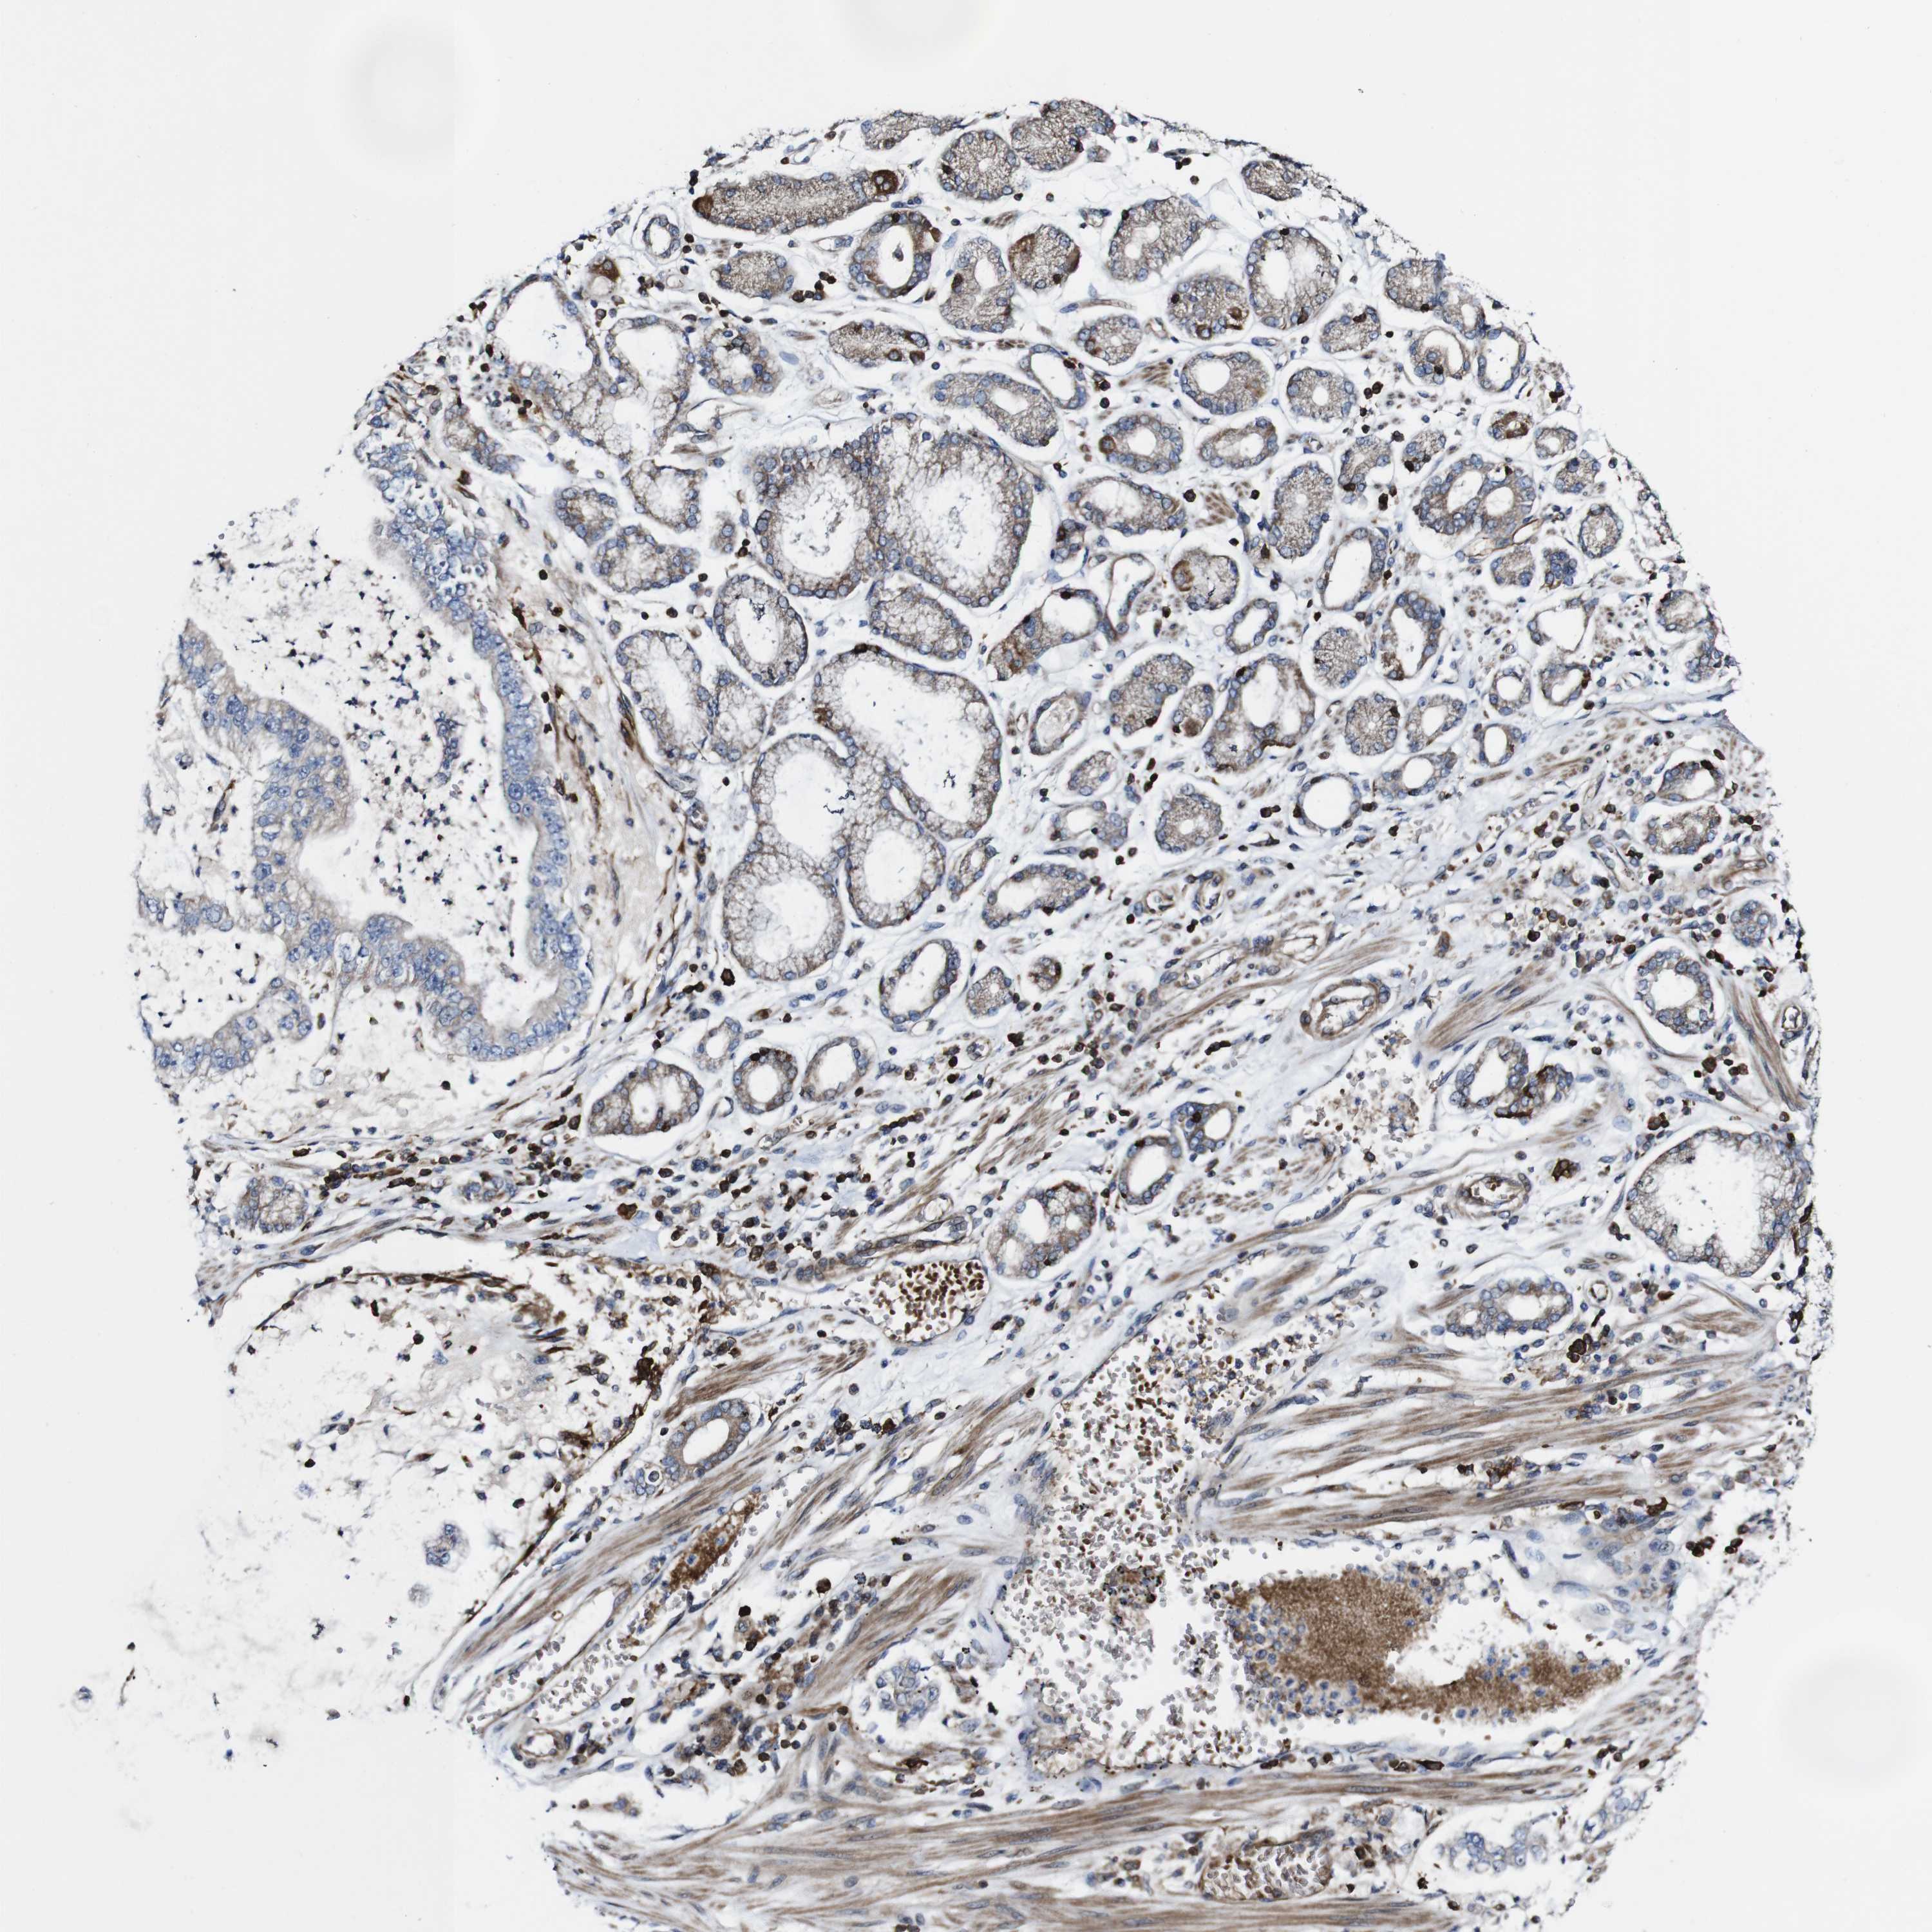

STOMACH CANCER - Protein expressioni

A mouse-over function shows sample information and annotation data. Click on an image to view it in a full screen mode. Samples can be filtered based on level of antibody staining by selecting one or several of the following categories: high, medium, low and not detected. The assay and annotation is described here.

Note that samples used for immunohistochemistry by the Human Protein Atlas do not correspond to samples in the TCGA dataset.

Antibody stainingi

Antibody staining in the annotated cell types in the current human tissue is reported as not detected, low, medium, or high, based on conventional immunohistochemistry profiling in selected tissues. This score is based on the combination of the staining intensity and fraction of stained cells.

Each image is clickable and will lead to virtual microscopy that enables deeper exploration of all samples and also displays staining intensity scores, fraction scores and subcellular localization as well as patient and tissue information for each sample.

Antibody HPA040820

Antibody CAB013089

Staining

High

Medium

Low

Not detected

Intensity

Strong

Moderate

Weak

Negative

Quantity

>75%

75%-25%

<25%

None

Location

Nuclear

Cytoplasmic/membranous

Cytoplasmic/membranous,nuclear

Adenocarcinoma, NOS